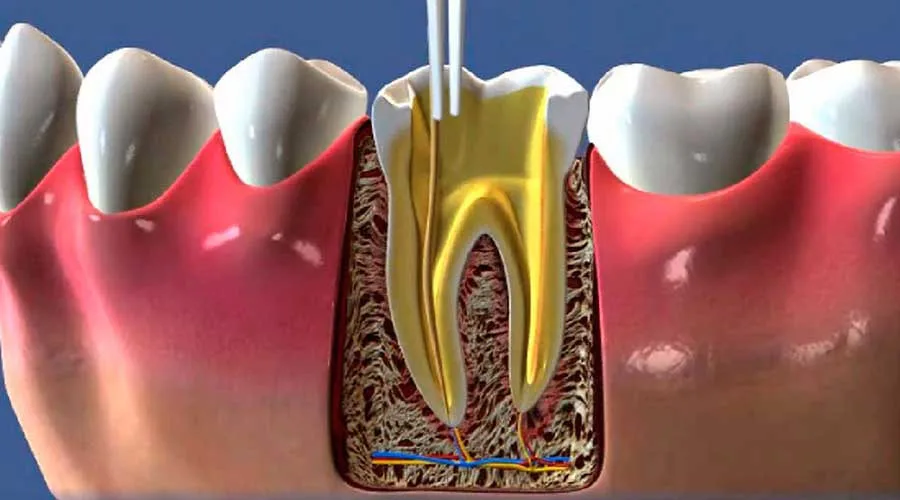

Na primeira visita, o paciente passa por uma avaliação detalhada para identificar a condição real da polpa dentária. O cirurgião discutirá as opções para preservar o dente natural, focando na eliminação total de infecções.

O acompanhamento pós-procedimento é indispensável para observar a cicatrização e a saúde da arcada. Seguir as recomendações de zelo é o que permite que o resultado seja duradouro e protegido contra novas intercorrências.